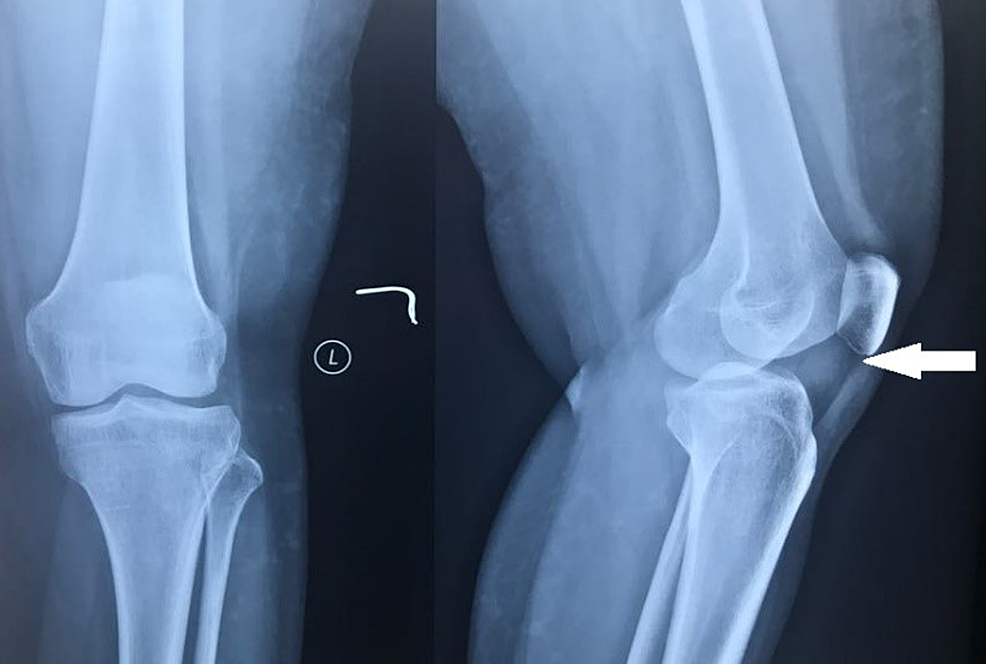

Knee Fat Pad Injury Symptoms. The fat pad is meant to slide and move as you bend and straighten your knee, but sometimes its movement gets restricted due to swelling or thickening or scar tissue, causing it to get pinched. Activities that involve frequent bending or extending of the knee joint, such as. fat pad impingement of the knee, also called hoffa's syndrome, is a common cause of pain in the front of the knee. It is situated deep to the patella tendon below your knee cap area and will often swell. what are the common symptoms? signs & symptoms. The pain is usually localised on either side of the kneecap, directly beneath it, or, occasionally, behind the patellar tendon. However, we should differentiate this condition from other causes like patellar tendonitis or patellofemoral arthritis. ♦ overuse or repetitive stress: the symptoms of hoffa’s fat pad impingement typically present with pain in the anterior (front) region of the knee. fat pad impingement is when your infrapatellar fat pad is pinched (impinged) between your kneecap and thigh bone or between your thigh bone and shin bone.

fat pad impingement of the knee, also called hoffa's syndrome, is a common cause of pain in the front of the knee. The fat pad is meant to slide and move as you bend and straighten your knee, but sometimes its movement gets restricted due to swelling or thickening or scar tissue, causing it to get pinched. The pain is usually localised on either side of the kneecap, directly beneath it, or, occasionally, behind the patellar tendon. It is situated deep to the patella tendon below your knee cap area and will often swell. signs & symptoms. Activities that involve frequent bending or extending of the knee joint, such as. what are the common symptoms? the symptoms of hoffa’s fat pad impingement typically present with pain in the anterior (front) region of the knee. fat pad impingement is when your infrapatellar fat pad is pinched (impinged) between your kneecap and thigh bone or between your thigh bone and shin bone. ♦ overuse or repetitive stress:

Knee Fat Pad Injury Symptoms the symptoms of hoffa’s fat pad impingement typically present with pain in the anterior (front) region of the knee. fat pad impingement is when your infrapatellar fat pad is pinched (impinged) between your kneecap and thigh bone or between your thigh bone and shin bone. what are the common symptoms? the symptoms of hoffa’s fat pad impingement typically present with pain in the anterior (front) region of the knee. The pain is usually localised on either side of the kneecap, directly beneath it, or, occasionally, behind the patellar tendon. It is situated deep to the patella tendon below your knee cap area and will often swell. fat pad impingement of the knee, also called hoffa's syndrome, is a common cause of pain in the front of the knee. Activities that involve frequent bending or extending of the knee joint, such as. signs & symptoms. The fat pad is meant to slide and move as you bend and straighten your knee, but sometimes its movement gets restricted due to swelling or thickening or scar tissue, causing it to get pinched. ♦ overuse or repetitive stress: However, we should differentiate this condition from other causes like patellar tendonitis or patellofemoral arthritis.